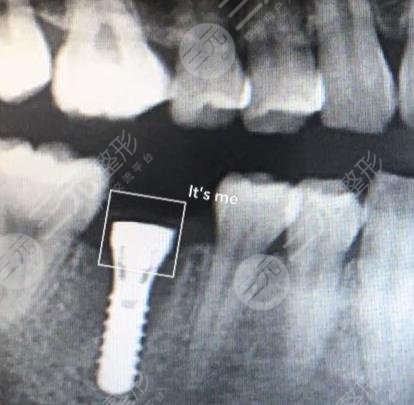

我在家人的陪同下来到医院做诊疗,里面的医生护士,态度都极为的亲切,医生查看以后建议我采用钛合金种植牙,钛合金和人体有较好的相容性,跟真牙并没有太大的差异,较重要的是,其稳定性较高,可以长期存在于人体,功能性较好。

种植牙说白了,就是装入一个义齿,不过与普通的义齿不同,这个牙齿不论是从外观以及功能性上都和真实的牙齿并没有太大的差别。在口腔医院这个种植过程主要分两步进行,第1步是牙根的植入,第2步是牙冠的镶嵌。整个过程,医生给我留下极为深刻的印象,他会仔细的告知于我他要进行哪个步骤,就让我安心不少,毕竟在看牙的时候,人或多或少的会有一种恐惧感。

这一操作极大的消除了我的恐惧感,医生护士的技术极为的娴熟,整个过程较为的利落。种植牙做完后,口腔并没有任何的不适感,正如医生所言总值好的牙齿,功能性较好,吃冷的,甜的都没有任何的感觉。不过,医生后面也嘱咐我要定期的看牙,以免牙齿发生严重龋坏。在这里我也要建议所有的小伙伴在看牙的时候,一定要选择一家正规的机构去做治疗,而日常生活当中也要注意保护牙齿。